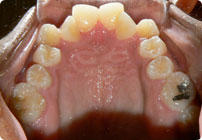

Femenino

Antes

Caso: 12 años

Adolescente: Clase II

Dental Maxilar Protrusion

Extract U4’s/L5’s

4 series de alambres:

.016″, 022″, .0215″ x .028″, .019″ x .025″ Trenzado

Elástico clase 2 2oz. TP amarillos y verdes

Retenedores: Interior Fijo de TMA y Hawley en superior

Tiempo de tratamiento: 15 Visitas